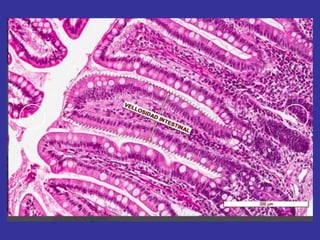

células plasmáticas

Derivadas de los LINFOCITOS B

En los tejidos conjuntivos su vida media es de

10 a 20 días. Su función es sintetizar y secretar

los anticuerpos (proteínas )

inmunoglobulinas. Ig

Su número aumenta en los tejidos con

procesos inflamatorios crónicos (parasitismo).

Abundan en la mucosa digestiva,

incrementándose durante la digestión, en los

órganos genitales durante el embarazo

A-Celulas plasmáticas inflamación crónica